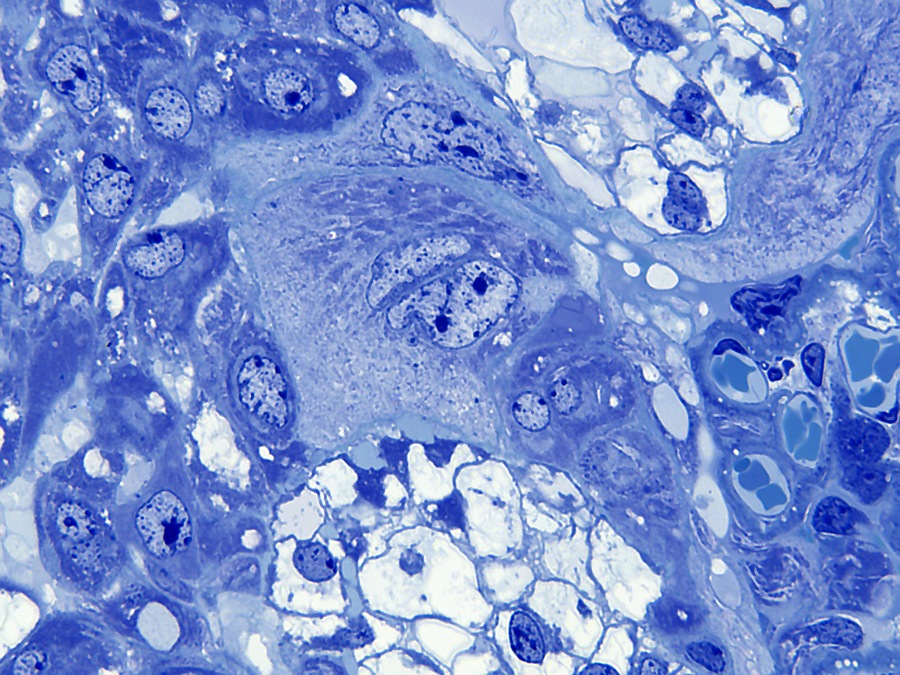

De muis heeft een hemochoriale placenta waarbij maternaal bloed in contact staat met foetaal chorion via een labyrintische laag (mensen hebben een vergelijkbaar type placentatie). De placenta bestaat uit maternale en embryonale lagen. De van het moederdier afkomstige laag is de decidua, die zich ontwikkelt uit het endometrium. De decidua bestaat uit twee delen: de decidua basalis en de decidua capsularis. De basalis heeft een rijk vasculair netwerk en bestaat uit losjes aanhangende onregelmatige grote vacuolate cellen met verschillend gevormde kernen van verschillende grootte.

De decidua wordt van de embryonale labyrintische zone gescheiden door de junctionele zone. De junctionele zone bevat maternale bloedvaten (veneuze drainage), trofoblastreuscellen en spongiotrofoblastcellen. Trofoblastcellen zijn over het algemeen erg groot met bizar gevormde of meervoudige kernen. Reusceltrofoblasten zijn, zoals hun naam al zegt, erg groot - tot 100 µm in diameter en bevinden zich het dichtst bij de decidua. Spongiotrofoblasten zijn fagocytisch[6] en kunnen gefagocytiseerde erytrocyten bevatten en bevinden zich dichter bij de labyrintische zone. De labyrintische zone bestaat uit nauw tegenover elkaar liggende foetale en maternale bloedkanalen. De foetale bloedkanalen zijn bekleed met dunne endotheelcellen en bevatten grote onrijpe gekerfde rode bloedcellen, terwijl de maternale bloedkanalen bekleed zijn met grote labyrintische trofoblastcellen.

Reusceltrofoblastcellen[3] zijn betrokken bij de modulatie van de maternale vasculatuur van de decidua en ze produceren verschillende placenta-specifieke hormonen die lijken op het hypofysehormoon prolactine[6]. Dit zijn onder andere Pl-1, Pl-2 (placentalactogeen) en proliferine, die uitsluitend door reuscellen worden uitgescheiden. Pl-1 en Pl-2 moduleren de activiteit van de eierstokken door de productie van luteaal progesteron te stimuleren, wat essentieel is voor het behoud van de zwangerschap. Bovendien zijn Pl-1 en Pl-2 betrokken bij de controle van de borstklierontwikkeling.